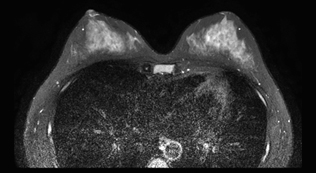

無痛乳房MRI

DWIBSとは:水分子の動きを画像化し、がん細胞を白く浮かび上がらせる技術。

乳腺MRIへの応用:「ドゥイブス・サーチ」と呼ばれ、乳房を圧迫せず痛みなく検査可能。放射線被ばくゼロ、造影剤不要。

精度:マンモグラフィよりも高感度で、特にデンスブレスト(高濃度乳腺(日本人女性に多い))に適している。

検査時間:10〜15分程度。着替えのみで準備不要。

対象:マンモグラフィが苦手な方、乳がん家族歴がある方、高濃度乳腺の方に有用。

乳がんドックは

「痛みゼロ・被ばくゼロ・高精度」

という三拍子揃った検査で、特に日本人女性に多い高濃度乳腺に適した方法です。

≪ 無痛乳房MRIの特徴 ≫

マンモグラフィーのように挟むのではなくベットにうつ伏せに寝て、乳房型にくり抜かれた穴に乳房を入れて撮影することで、痛みはまったくありません。 |